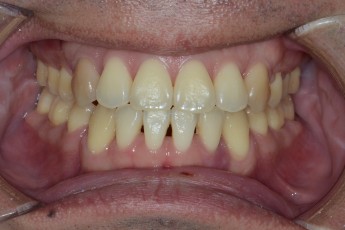

Before

After